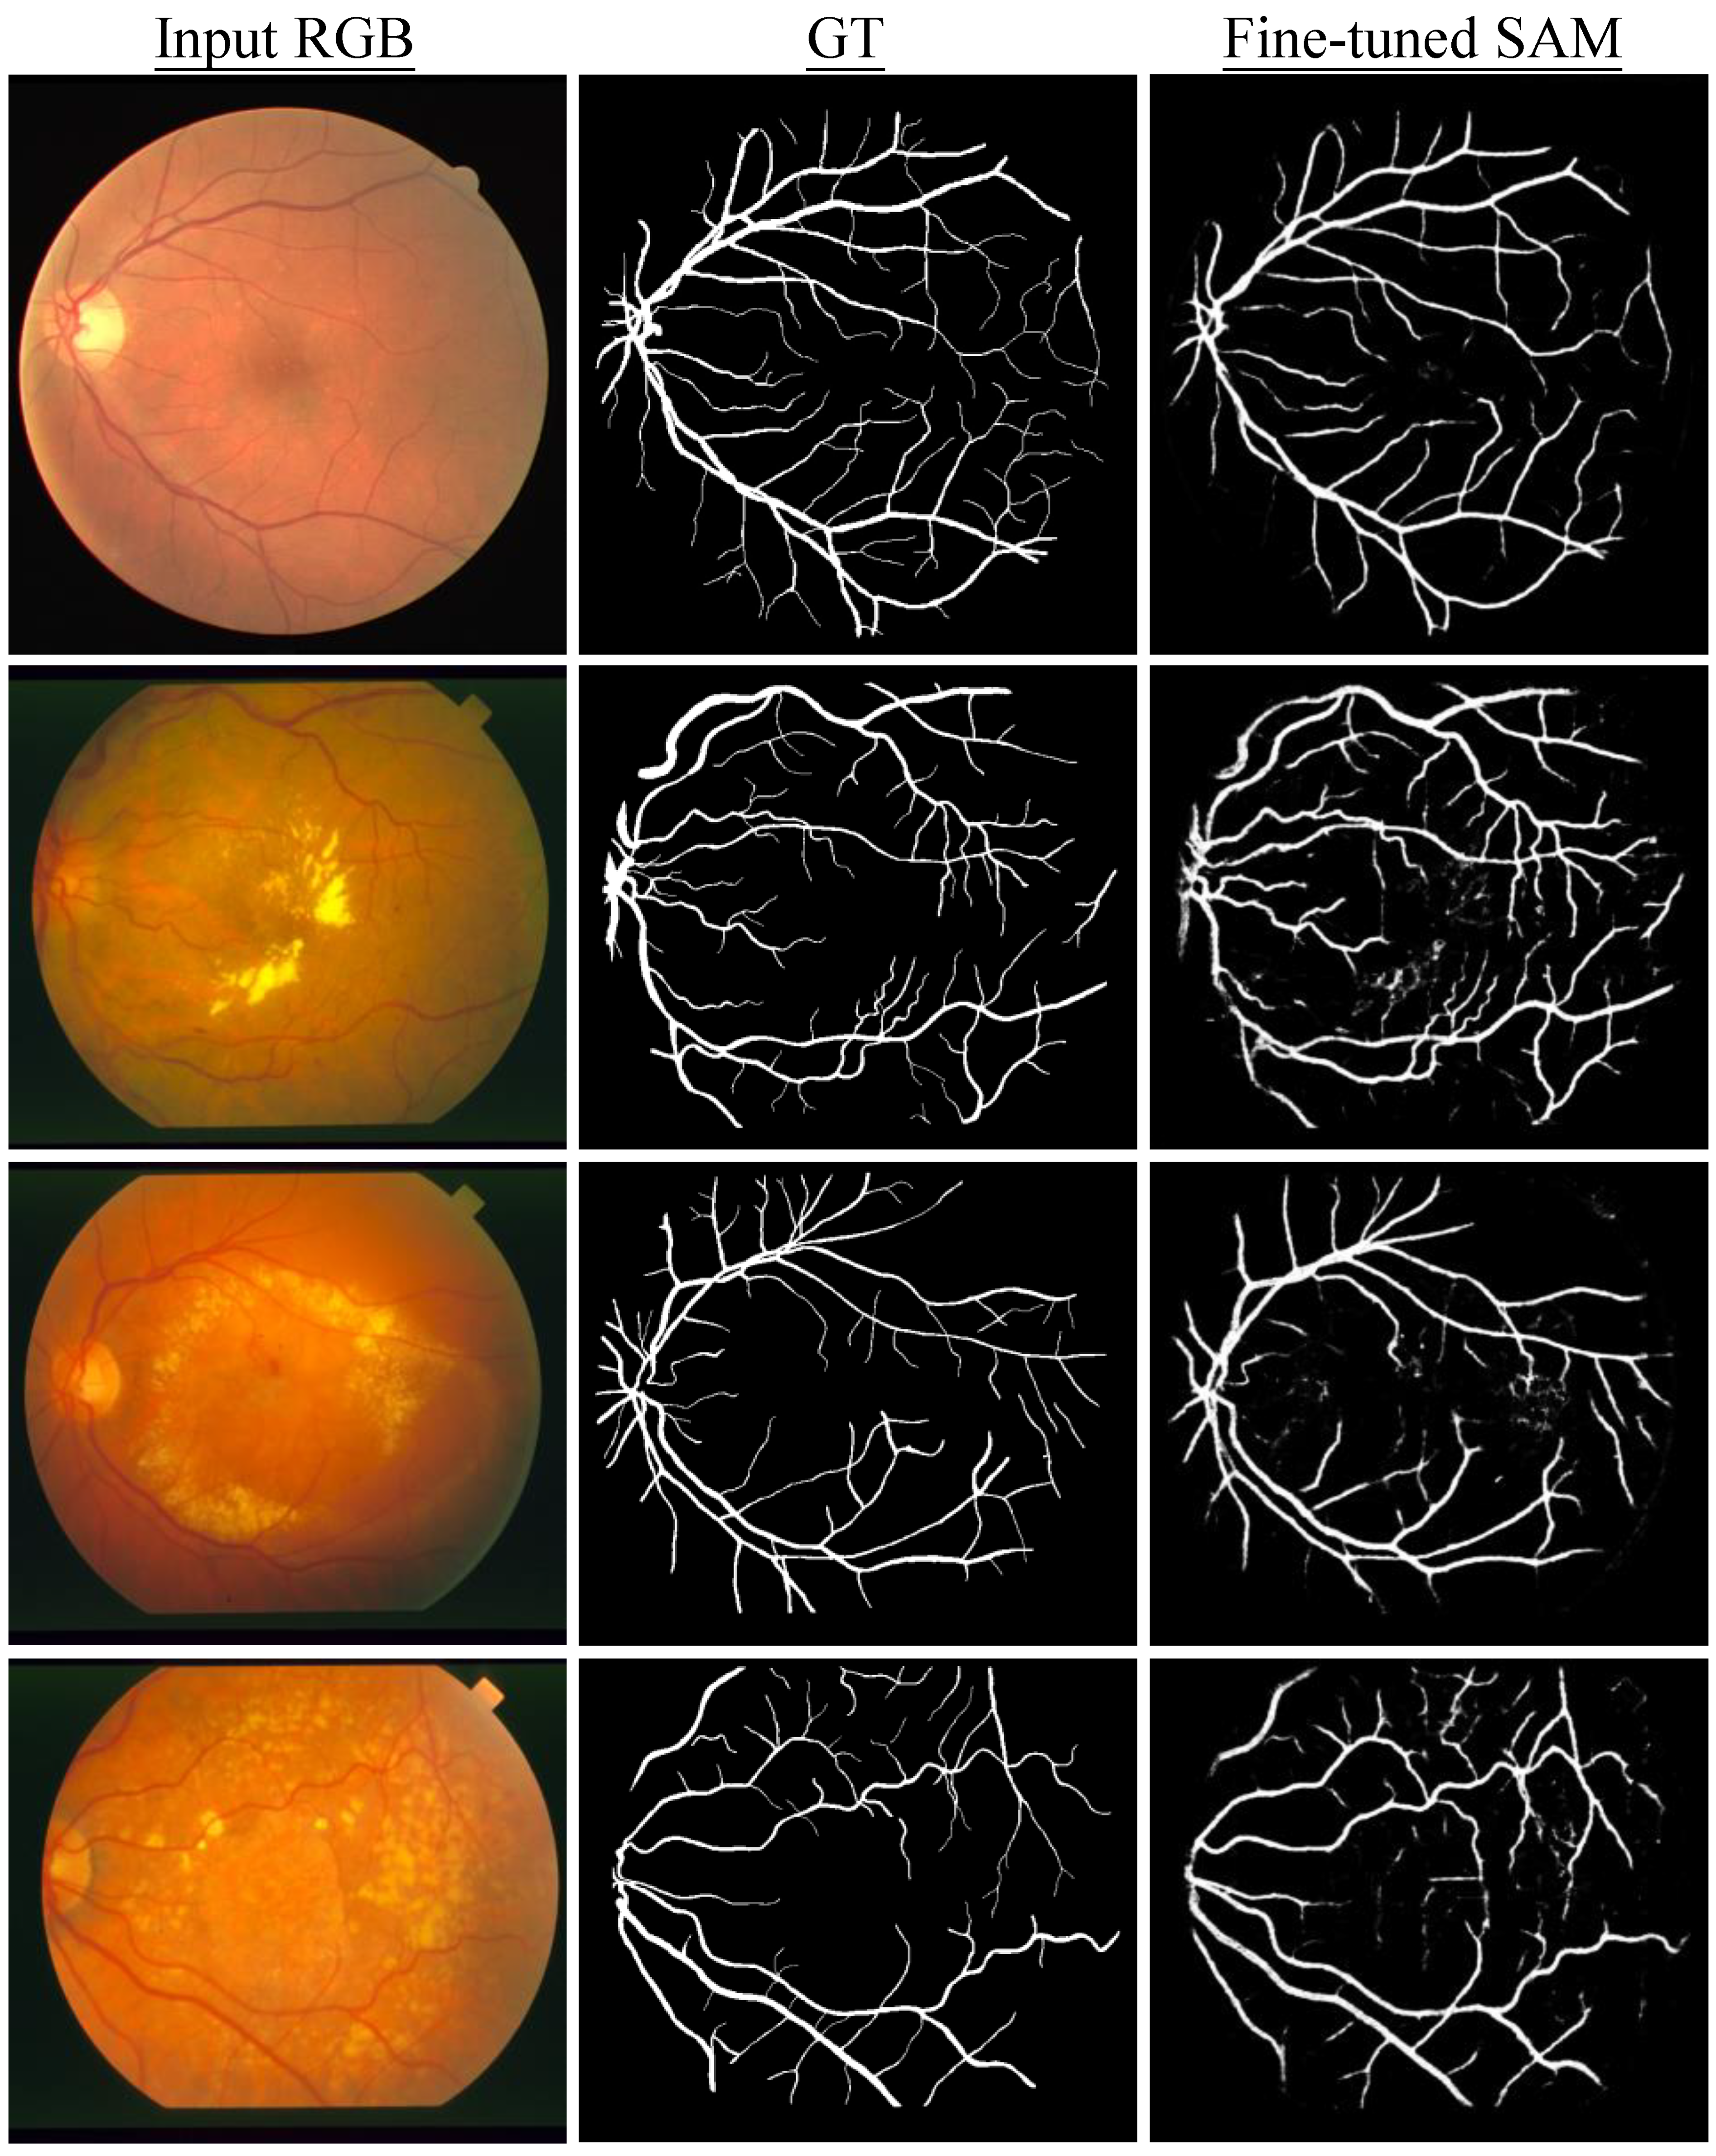

We also used SAM to segment vessels in fundus images. However, the experiments revealed that zero-shot SAM is not able to accurately segment retinal blood vessels, despite the manual provision of additional prompts focused on areas where visibility of vessels is pronounced. At the current stage, we conjectured that the segmentation of continuously branching structures, such as blood vessels in medical images and tree branches in nature images, presents a challenge for SAM. As shown in Figure 3, it is found that SAM encounters difficulties in accurately identifying vessels as distinct segmentable objects. Therefore, we further conducted fine-tuning of SAM to examine its potential of improving segmentation results. To fine tune SAM (SAM ViT-B in this experiment), we utilized SAM adapter [37], a task-specific fine-tuning method proposed for SAM. Specifically, 20 image-mask pairs were selected from the Digital Retinal Images for Vessel Extraction (DRIVE) dataset [38] to fine-tune SAM’s mask decoder. As the fine-tuning was fully supervised, there was no prompt provided and the ground truth masks were used to supervise the training. The entire fine-tuning process was trained with the AdamW [39] optimizer. The learning rate was set to 2 × 10 4 with a total of 20 training epochs. The batch size was one with the input image size of 1024 × 1024 pixels. A total of four datasets were utilized for the quantitative assessment. Three of them are the official test sets from their respective datasets. The official training set from the STARE dataset [40] was also employed for testing as its own test set is lacking. As shown in Table 10, the fine-tuned SAM demonstrated substantial improvements in both the Dice and IoU metrics. Noticeably, the Dice scores increased by at least 200 percent relative to its zero-shot counterpart where vessels were segmented by manually providing the prompt. Furthermore, the improvements of IoU were even more pronounced. In addition, as illustrated in Figure 4. The segmentation results of SAM after fine-tuning almost perfectly match with ground truth in some cases and only some tiny parts at the terminal ends of vessels are missing, demonstrating the potential of SAM for precise medical image segmentation after a domain-specific fine-tuning.

Figure 4. Segmentation samples of SAM fine-tuned on retinal vessels. Each row from left to right is the initial input image, ground truth mask and prediction of fine-tuned SAM. The column from top to bottom shows retinal images from four different datasets.